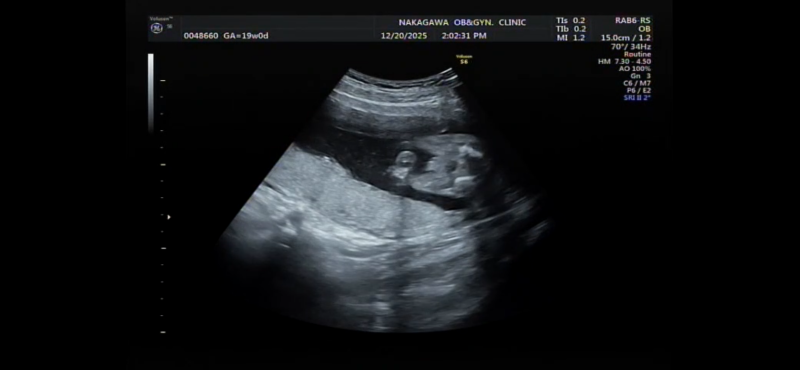

19週になりましたが、まだ性別がわかりません。 正月に家族とも話したいなーと思っているのですが 次の検診が年明けなので もし分かるのであれば教えて欲しいです!

へその緒が近くにあるのでわかりづらく、、

確定はできないのはわかっていますが多分どっちかでも知りたいです、、!

お腹の赤ちゃんの性別についてですね。

添付をしてくださった画像を拝見いたしました。

男の子のシンボルとなりそうなものがありそうに見えあたり、なさそうにも見えたりと、どちらかということもお返事がしにくい状況でした。